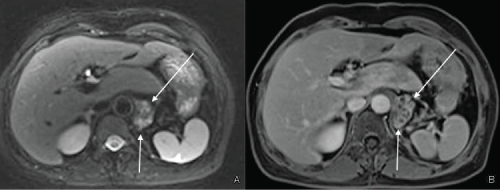

Contrast Enhanced abdominopelvic Magnetic Resonance (MR) confirmed CT findings (Figure 5 and Figure 6).

Figure 5: Contrast enhanced MRI: Lesion of the gastric fundus T2 fat saturated axial image (A) and T1 fat saturated post-contrast image (B) showing a paraaortic lesion with multicystic appearance (arrows). View Figure 5

Figure 6: Contrast enhanced MRI: Paraduodenal lesion T2 fat saturated axial image (A,B), coronal HASTE image (C), post-contrast coronal T1 fat saturated (D) showing a well-defined lesion with multicystic appearance (asterisks) with thick rim-like enhancement well visible in the delayed phase (in D). View Figure 6